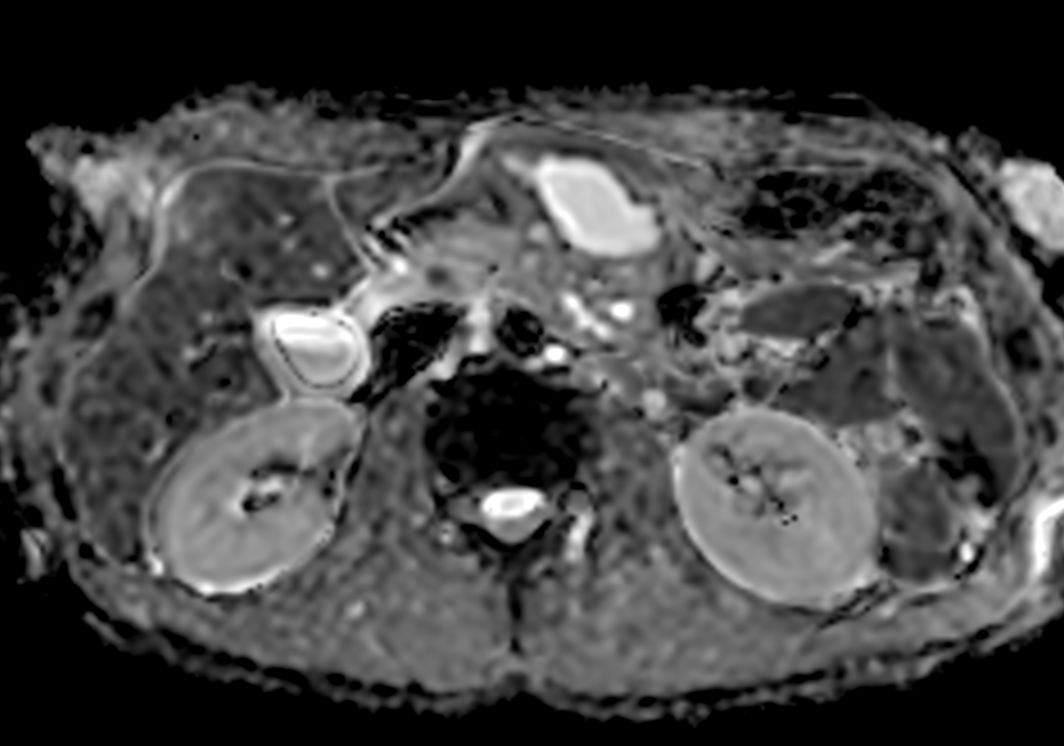

Axial DWI b10003mm slices

-

Axial DWI b503mm slices

Axial DWI b6003mm slices

Axial DWI ADC3mm slices

Axial DWI b504mm slices

Axial DWI b6004mm slices

Axial DWI ADC4mm slices